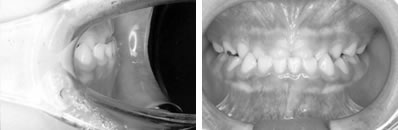

併用した長期経過症例 4歳

治療開始時年齢は6歳半でしたが、永久歯は1本もありませんでした。右上の乳歯Dから左上の乳歯Cまでが反対咬合の状況でした。

レントゲンの検査、家族暦などから骨格的な下顎前突の程度が大きいことがわかりましたので、オトガイ帽装置(チンキャップ)を使用することになりました。

この装置の使用効果についてはさまざまな論拠、発表がありますが、本院では直接的に下顎骨を小さくする効果は無いと考えています。しかしながら、他の装置の使用効果を高めたり、習癖を除去する効果があり、その結果上顎の本来の成長が得られて上下顎の大きさのバランス改善が得られると思われます。少しでも治療を楽しむため色付の装置も用意しています。

普段のかみ合わせのまま下顎を後ろに押し下げようと力をかけた場合、上顎前歯と下顎前歯がぶつかって上顎まで後ろに下げようとする力が働いてしまいます。そこで、チンキャップを使用する場合には前歯の干渉を避けるためにクリアプレートを併用しました。

1年後(7歳半)の口腔内 下顎前歯が抜け替わりましたが、反対咬合の状態です。

装置使用開始4ヶ月目には反対咬合が解消されています。